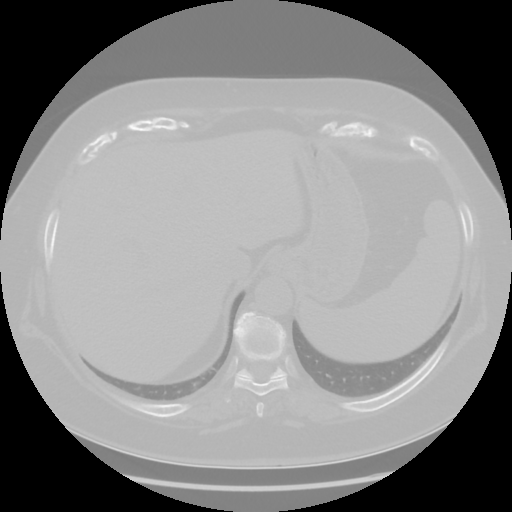

Generated VENOUS CT scan (A→B translation)

No window - Raw intensity values